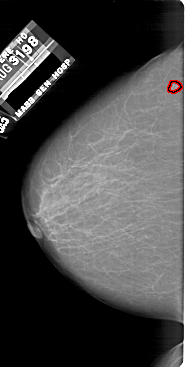

A_1805_1.LEFT_MLO

LEFT_MLO LINES 6241 PIXELS_PER_LINE 3271 BITS_PER_PIXEL 12 RESOLUTION 43.5 OVERLAY

FILE: A_1805_1.LEFT_MLO.OVERLAY

TOTAL_ABNORMALITIES 1

ABNORMALITY 1

LESION_TYPE MASS SHAPE IRREGULAR MARGINS ILL_DEFINED

ASSESSMENT 4

SUBTLETY 1

PATHOLOGY BENIGN

TOTAL_OUTLINES 1

BOUNDARY